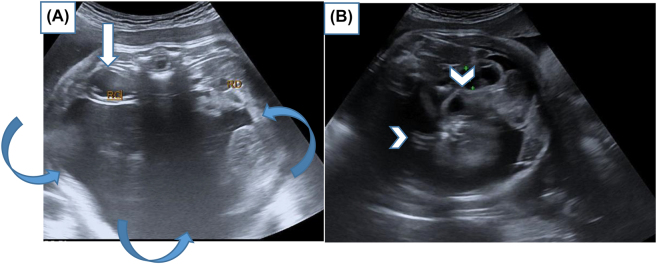

Objectives: Fetus-in-fetu is a rare congenital anomaly that occur secondary to abnormal embryogenesis in a diamniotic monochorionic pregnancy. Its diagnosis can be accurately made by imaging ultrasonography, radiography, computed tomography, or magnetic resonance imaging. Differential diagnosis is an important issue because FIF, teratoma and cystic meconium peritonitis are very different in terms of their respective disease courses.

Case presentation: This is an interesting rare case of a 22-year-old pregnancy woman, presented for a routine antenatal ultrasound. The diagnosis of a fetus-in-fetu was suspected, complete surgical excision of the lesion was performed and the diagnosis was histopathologically confirmed.

Conclusions: We describe also the common characteristic of FIF as revealed by prenatal and postnatal US, postnatal MRI, and the operative findings.